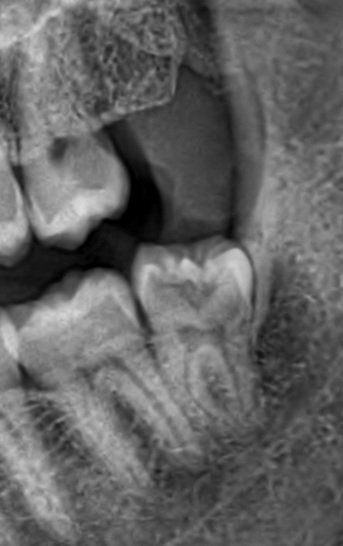

Мъдрецът беше така. Леко криви корени и заради това излезе трудно. Няма от какво да се притеснявате. Извадих всичките си четири мъдреца и само този беше по-труден. Болки имах след това, но не бяха твърде силни. По-силно ме е болял зъб с пулпит. Така че действайте, колкото повече отлага човек, толкова по-вероятно е да мъдрецът да започне да се руши, което прави ваденето му по-трудно.

Моят беше подобен на твоя, но беше легнал хоризонтално към кътника, почти изцяло ретиниран. Лекаря го разряза на две части и така го извади. Орерацията беше 30-40 минути макс. Във ВМА София го вадих. Предполагам, че и твоя така ще го режат. Този хирург от Пловдив не го знам, тъй като не съм от този край, но след като има добро име и се води най-добрия, не се притеснявай, всичко ще е наред!